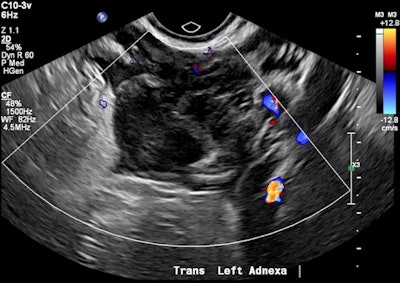

A 32-year-old female presented with severe constant left lower abdominal pain, per vaginal spotting and nausea. A pelvic ultrasound performed at six weeks' gestation demonstrated a viable intrauterine gestation and a small perigestational hematoma. A heterogeneous mass was noted abutting the left ovary. It featured peripheral vascularity, but no internal vascularity. There was small-volume pelvic free fluid with low-level internal echoes consistent with hemoperitoneum (see three images below).

Left adnexal heterogeneous mass with an echogenic tubal ring sign (blue arrows) adjacent to the left ovary (red arrows).

Pelvic free fluid with low-level internal echoes consistent with hemoperitoneum.The patient was given a preliminary diagnosis of a hemorrhagic corpus luteal cyst. Heterotopic pregnancy was initially considered but thought less likely. The treating team opted for conservative management with a view to perform short-term follow-up ultrasound. Follow-up imaging two days later demonstrated a persistent left adnexal mass with interval increase in hemoperitoneum volume. The mass was seen to move separately to the left ovary on transvaginal/abdominal palpation maneuvers.